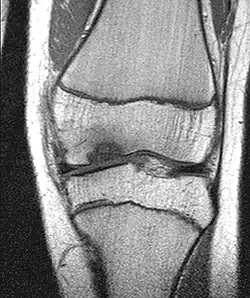

Die Erkrankung kann zufällig auf einem Röntgenbild entdeckt werden, das nach einem Unfall von der Knieregion, vom Sprunggelenk oder vom Ellbogen angefertigt wird. Bei typischen Beschwerden von aktiven Kindern und Jugendlichen kann mit einem solchen einfachen Röntgenbild die eindeutige Diagnose schon gestellt werden, weil der veränderte Knochen unterhalb der Gelenkoberfläche an typischer Stelle in der Oberschenkelrolle am Knie identifiziert werden kann. Manchmal kann eine sogenannte Tunnelaufnahme mit gebeugtem Knie die Schädigungszone noch besser zeigen. Zur genaueren Analyse sollte eine Kernspintomographie (MRT) durchgeführt werden. An den dabei erzeugten Bildern lässt sich die Lage und Größe des Befundes, die Tiefenausdehnung und vor allem eine Beteiligung des darüberliegenden Knorpels genau ausmessen. Es sind damit auch Aussagen zur Stabilität des Befundes zu treffen. Daraus ergeben sich dann entscheidende Anhaltspunkte für therapeutische Konsequenzen. Für die Verlaufsbeurteilung der Erkrankung eignet sich am besten das MRT, aber ggf. auch wieder die einfache Röntgenuntersuchung. Aufgrund der extrem hohen Kosten für das MR in den USA werden die Verläufe dort bis heute weitgehend nur mit Röntgenbildern dokumentiert, was zu eigenen Empfehlungen zur Verlaufsbeurteilungen führt. Generell wären aber die MR-Untersuchungen das Verfahren der Wahl. Sie erlauben eine differenzierte Beurteilung der unterschiedlichen Kriterien für Ausheilung, Instabilität und drohende Dissektion. Untersuchungen mit Sonographie können zuverlässige, aber nur orientierende Befunde am Femurkondylus erheben. Es ist damit zum Beispiel ein schneller, kostengünstiger und sicherer Ausschluss des Befalls auch der Gegenseite möglich.